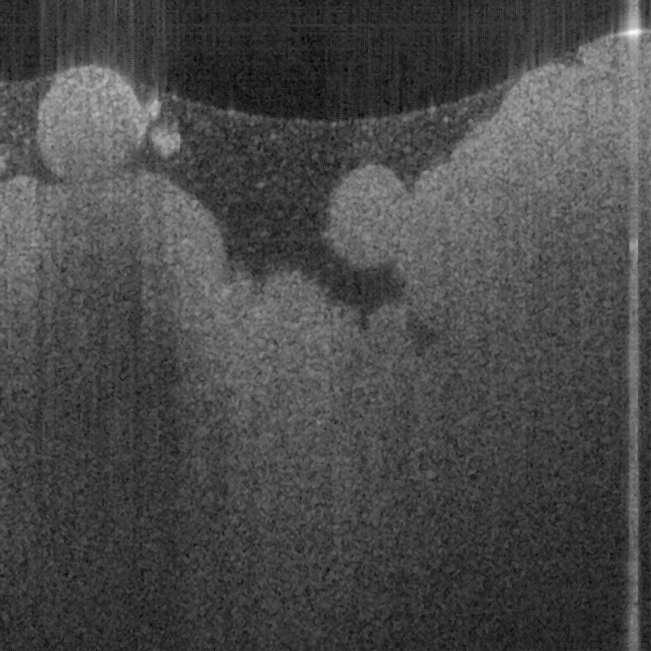

Fig. 18 shows ex vivo images of heart atrium (a, b), artery (c) of mice, and heart atrium (d, e, f)

of pig with forward-view probe with ball lens #16 acquired by our catheter-based complex

SS-OCT using our 3x3 Mach-Zehnder interferometer with unbalanced differential detection

technique with image size of 2x2mm. The shapes and structures of these internal organs of

small and large animals are viewed clearly from these OCT images.

Fig. 18. Ex vivo images of heart atrium (a, b), artery (c) of mice, and heart atrium (d, e, f) of

pig acquired by our catheter-based complex SS-OCT using our 3x3 Mach-Zehnder

interferometer with unbalanced differential detection technique.